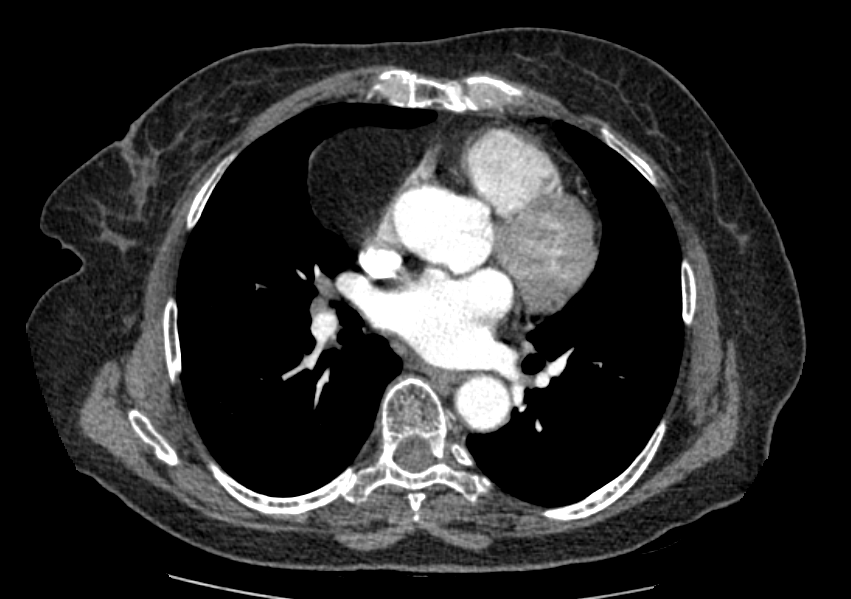

< Chest CT >